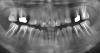

Dr. Surkin Опубликовано 3 июня, 2009 Поделиться Опубликовано 3 июня, 2009 Спасибо за ответ, но еще в школе у меня было 4ре коронки, и они полностью были покрыты керамикой, эффекта гнилого зуба не было. Да и вообще никогда не сталкивалась с тем, что коронки такими бывают, уж простите.В то время это были обыкновенные коронки, не из диоксида циркония. поэтому, я мягко говоря и удивилась, когда вышла из кабинета. Обычно перед фиксацией коронок доктор надевает их на зубы, показывает пациенту и спрашивает - "Ну как? Нравится?"или хотя бы- "Ну как? Пойдет?" У Вас такого не было??Теперь, когда коронки фиксированы, их никак уже не снимешь, кроме как распилив пополам. Так что если эстетика не устраивает - придется делать новые коронки. Рекомендую также сделать панорамный рентгновский снимок и выложить здесь на форуме - посмотрим, может какие еще вопросы или рекомендации появятся. Ссылка на комментарий

Jasmin Опубликовано 3 июня, 2009 Автор Поделиться Опубликовано 3 июня, 2009 Обычно перед фиксацией коронок доктор надевает их на зубы, показывает пациенту и спрашивает - "Ну как? Нравится?"или хотя бы- "Ну как? Пойдет?" У Вас такого не было??Теперь, когда коронки фиксированы, их никак уже не снимешь, кроме как распилив пополам. Так что если эстетика не устраивает - придется делать новые коронки. Рекомендую также сделать панорамный рентгновский снимок и выложить здесь на форуме - посмотрим, может какие еще вопросы или рекомендации появятся. Спасибо за ответ и ...уфф....да.. такого не было, это врач, которому я доверяю (ла) безоговорочно, я и сама очень удивилась, что ничего никто не показал заранее, не сказал, не спросил, кроме удобно, не удобно. А сейчас, что уже делать, слезами горю не поможешь. На первые вопросы - был ответ, что парадонтоз и нельзя зуб под десну, но кто ж знал, что будет так ужасно... Виню себя - так много и долго мучаюсь с зубами и врачами и не должна была попасть в такую ситуацию. Снимок есть только старый, до протезирования, 6ка верхняя удалена, там мост, 4х зубов нет (выдрали еще в детстве, пытались исправить прикус), 5тые верхние депульпированы, под коронками уже. 5й нижний пересобран и тоже под коронкой. В общей сложности - 11 единиц коронок. Ссылка на комментарий

Dr. Surkin Опубликовано 3 июня, 2009 Поделиться Опубликовано 3 июня, 2009 Спасибо за ответ и ...уфф....да.. такого не было, это врач, которому я доверяю (ла) безоговорочно, я и сама очень удивилась, что ничего никто не показал заранее, не сказал, не спросил, кроме удобно, не удобно. А сейчас, что уже делать, слезами горю не поможешь. На первые вопросы - был ответ, что парадонтоз и нельзя зуб под десну, но кто ж знал, что будет так ужасно... Виню себя - так много и долго мучаюсь с зубами и врачами и не должна была попасть в такую ситуацию.Снимок есть только старый, до протезирования, 6ка верхняя удалена, там мост, 4х зубов нет (выдрали еще в детстве, пытались исправить прикус), 5тые верхние депульпированы, под коронками уже. 5й нижний пересобран и тоже под коронкой. В общей сложности - 11 единиц коронок. Хорошо бы новый еще снимок... Ссылка на комментарий

Jasmin Опубликовано 3 июня, 2009 Автор Поделиться Опубликовано 3 июня, 2009 Хорошо бы новый еще снимок... сделаю завтра, сегодня уж руки опустились совсем... там действительно еще много переделок было... по старому мало чего понятно. Это так называемая "гирлянда" - разновидность исполнения М/К коронки.плохой сплав,плохо отполирована,потому так и выглядит.была бы хорошая полировка - было бы у десны колечко из полированного металла. как на пальце.Чтобы хотеть такой эффект,надо мочь ставить коронки из диоксида циркония. гирлянда))) красивое ж блин название - у меня же четко сформировалось название - за ваши деньги, что угодно - даже эффект гнилых зубов) и после ничего не менялось? каналы-то хоть перелечивали? сделаю новый снимок, наверное будет понятнее...некоторые каналы перелечивали еще давно, когда сняли первые коронки, 3 пятых зуба вообще депульпировали, плюс 8ку - ну - лучше снимок, чтоб не тратить ваше драгоценное время)) Ссылка на комментарий